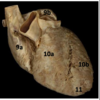

Identify #1

Pericardium

Identify #1

Atrioventricular mitral valve

Interventricular septum

Identify #10a

Right venticle

Identify #10b

Left ventricle